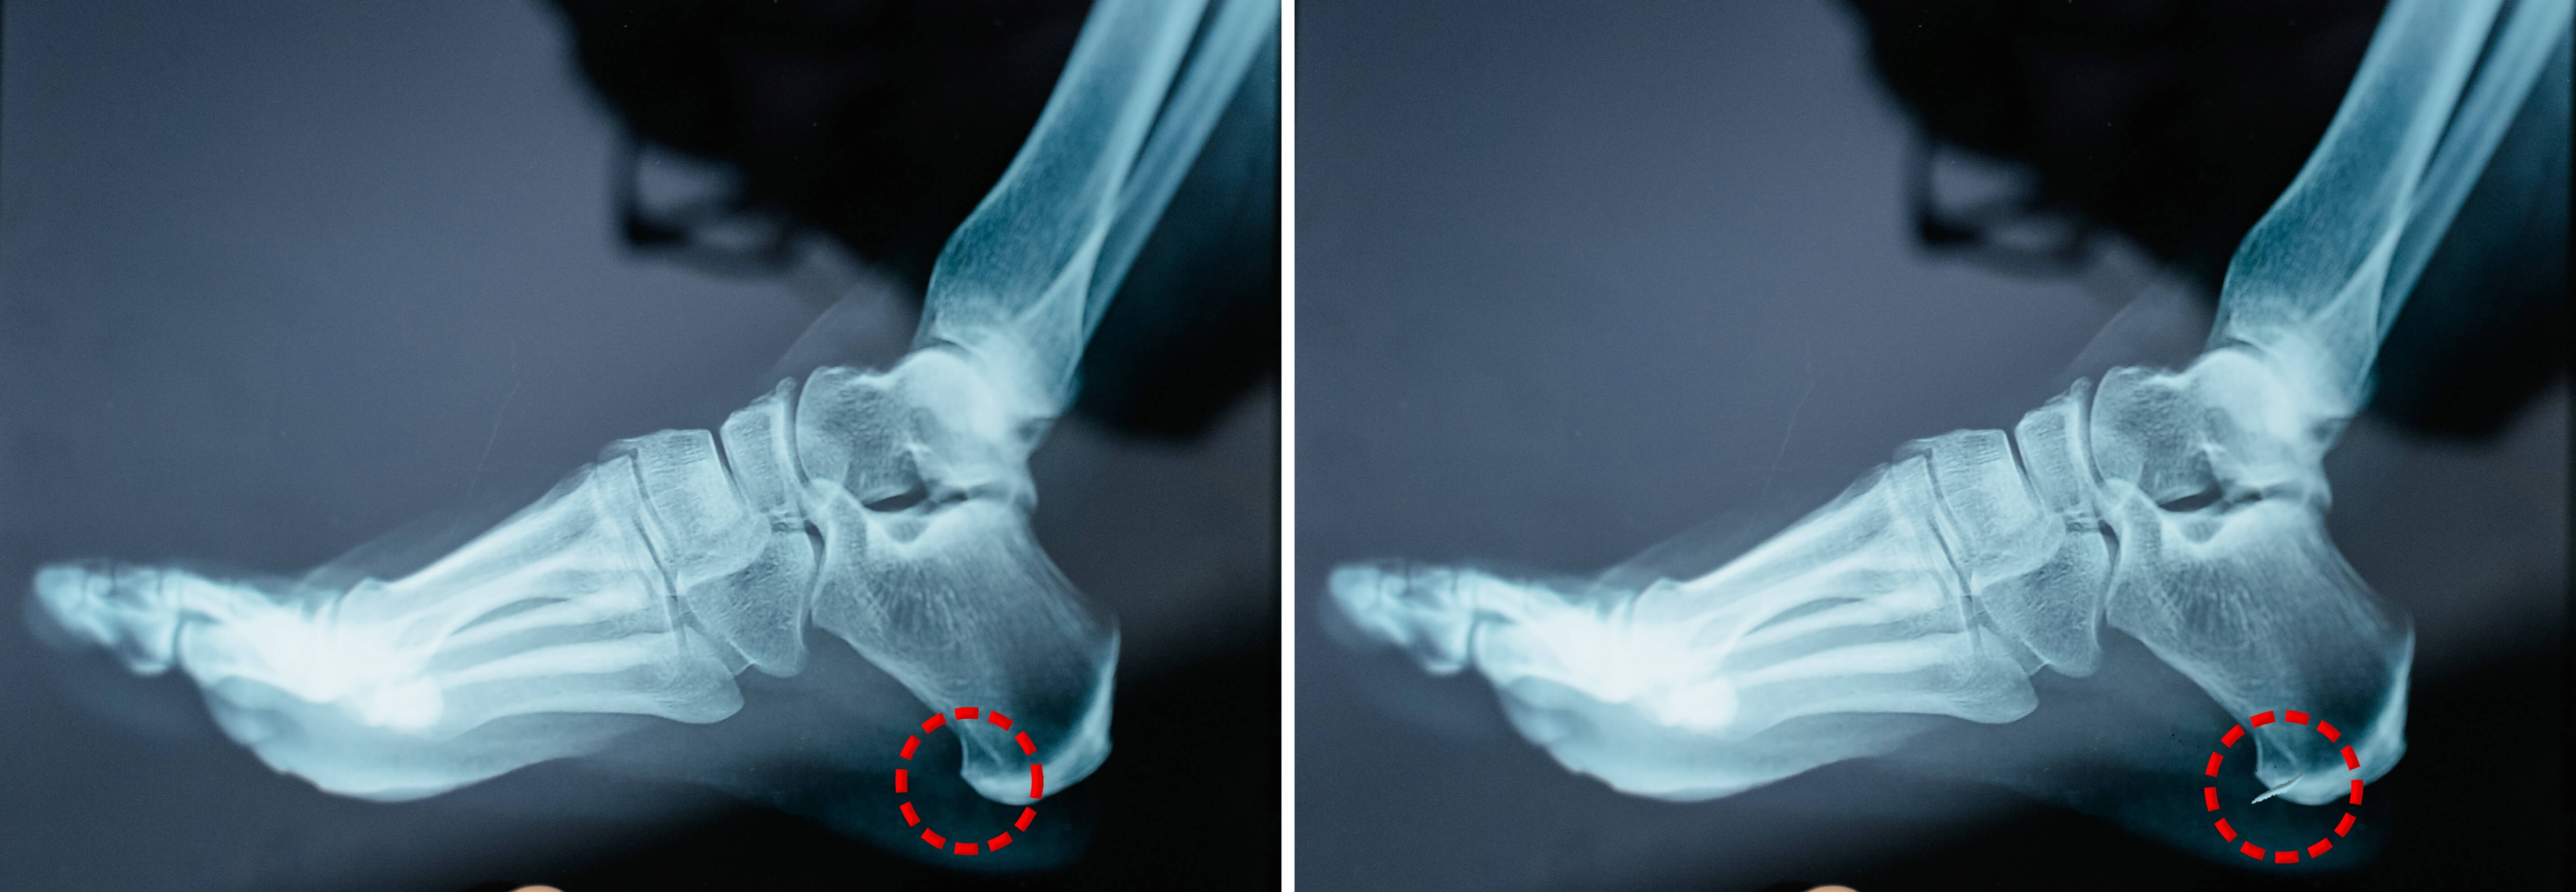

위의 두 사진의 차이가 보이시나요?

왼쪽 발은 정상인의 발이고 오른쪽 발은 뒤꿈치 쪽에 작은 뼈가 이상발육하여 생긴 족저근막염 발입니다.

이뼈가 인체의 자연쿠션인 발 뒤꿈치 근육을 자극하여 족저근막염을 초래하는 것입니다.

위의 엑스레이 사진에서 보듯 발 뒤꿈치의 뼈가 이상하게 자라 발 뒤꿈치를 자극하며 오는 통증입니다.